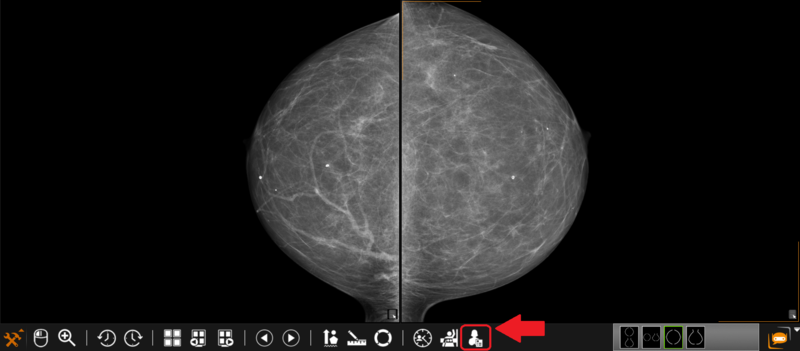

1.Click on the ‘Structural MG report’ button located on the toolbox panel: